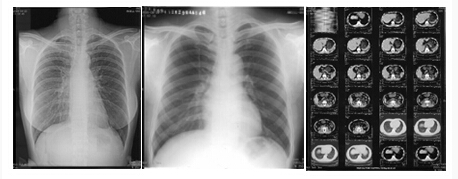

针对医院用户可以处理各式胶片,将传统的胶片扫描数字化后,自动生成DICOM3.0国际标准 格式图像,通过胶片数字化管理系统,可以方便地浏览、存储、打印图像和报告。拥有独特的诊断报告和专家系统功能,医生可以根据预先输入的专家模块快速生成 图文并茂的检查报告,操作软件简单,易学易用,节省成本,用很少的投入实现高科技的数字化的诊断,是医院实现无胶片化管理的*佳伙伴。

扫描样片